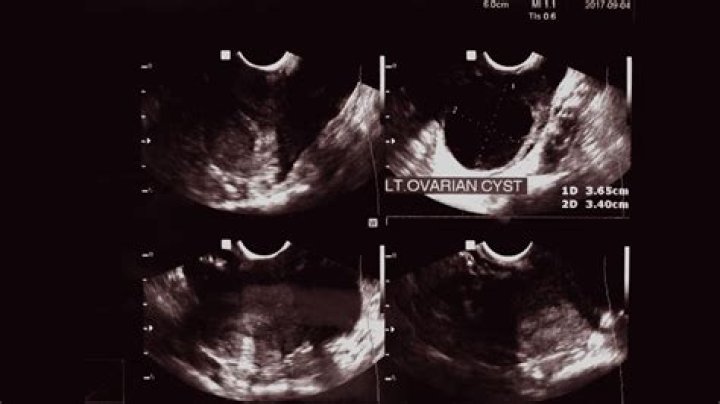

Ovarian cysts can sometimes be detected during a pelvic examination, although an imaging test, usually a pelvic ultrasound, is necessary to confirm the diagnosis. Computed tomography (CT) scan or magnetic resonance imaging (MRI) are also sometimes used, but less commonly.

If your gynecologist suspects that your symptoms could be due to ovarian cysts the best way to diagnose these cysts is through a pelvic exam or by performing an ultrasound. The ultrasound will allow your doctor to examine the abdomen in detail to see if cysts are present.

2. Ultrasound. An ultrasound can pinpoint the location, size, and makeup of ovarian cysts. ...